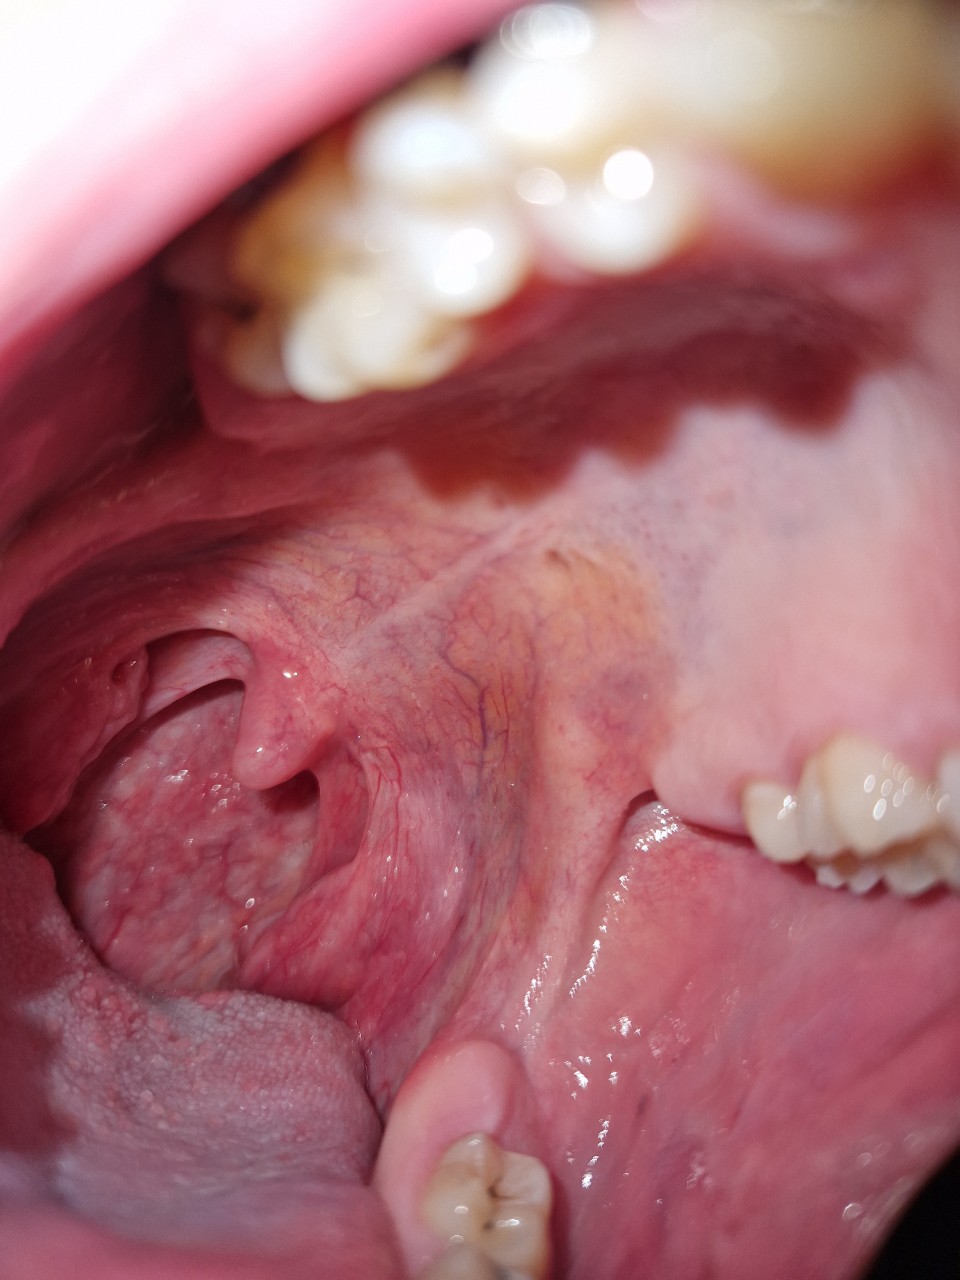

Плотное образование в ротоглотке

Здравствуйте, сегодня впервые заметил образование в области горла (визуально — на задней стенке глотки/вблизи небной дужки). На ощупь оно кажется плотным и неподвижным.

Не могу сказать, как давно оно появилось — раньше не обращал внимания. Не знаю, увеличивается ли оно и меняется ли по форме.

Боли нет, дискомфорта практически не ощущаю. Кровоточивости не было. Язв или повреждений визуально не вижу. Глотание не нарушено, голос не изменился. Слух без изменений.

Лимфоузлы на шее прощупываются, но они мягкие, подвижные и безболезненные.